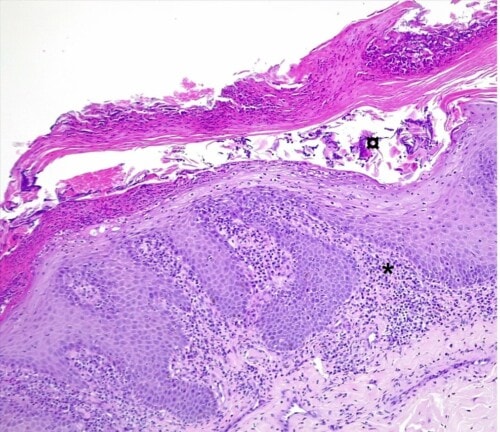

L’examen histologique des coupes de lésions croûteuses colorées à l’hématoxyline et à l’éosine révèle une hyperplasie parakératosique, avec de petites vésiculo-pustules intra-épidermiques contenant des éosinophiles et quelques cellules épithéliales acantholysées, un infiltrat lichénoïde avec des lymphocytes, des plasmocytes, des macrophages, des cellules dendritiques et des mélanophages dans les machons péri-annexiels. Aucun élément bactérien ou parasitaire n’est observé.

Figure 2: Photomicrographie. Vésiculo-pustules intra-épidermiques (¤) contenant des éosinophiles et quelques cellules épithéliales acantholysées, et un infiltrat lichénoïde (*) (H&E, x100). (H&E, x100)